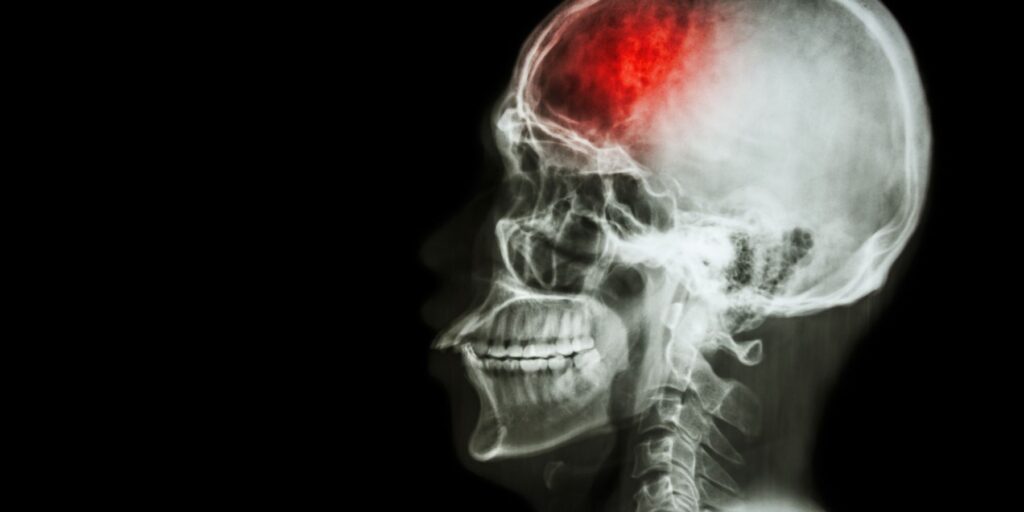

Sufrir un accidente cerebrovascular (ACV) es una experiencia desafiante tanto para el paciente como para su familia. La rehabilitación después de un ACV es crucial para recuperar la movilidad y mejorar la calidad de vida. Entendiendo el Proceso de Rehabilitación La rehabilitación post-ACV es un camino que requiere tiempo, paciencia y esfuerzo. Supone la colaboración […]